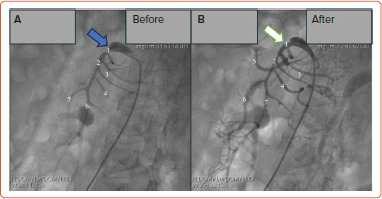

COVID-19 患者可能会出现急性肠系膜缺血。识别急性肠系膜缺血具有挑战性,尤其是最初的症状往往模糊不清,很容易被忽视。及早发现并立即干预以恢复血流,可以避免这些严重后果的发生。本报告介绍了两例严重急性呼吸综合征冠状病毒 2 感染后出现肠系膜上动脉(SMA)血栓形成的病例。CT 扫描显示两名患者均有肠系膜上动脉血栓形成,但无肠道坏死迹象。经血管造影确诊后,对患者进行了血管内介入治疗,并放置了自膨胀支架。随访6个月后,两名患者在接受双重抗血小板治疗后仍无症状。COVID-19 患者的非典型胃肠道表现应引起对不常见并发症(如 SMA 血栓形成)的怀疑。对于不伴有肠坏死的 SMA 闭塞,血管内治疗是一种可行的治疗方法。

COVID-19 patients may experience acute mesenteric ischaemia. Identifying acute mesenteric ischaemia is challenging, particularly as initial symptoms are often vague and easily overlooked. Early detection and immediate intervention to restore blood flow can prevent these severe consequences. Presented in this report are two cases of superior mesenteric artery (SMA) thrombosis following severe acute respiratory syndrome coronavirus 2 infection. CT scans demonstrated SMA thrombosis in both patients, with no evidence of bowel necrosis. Endovascular intervention with self-expanding stent placement was performed after angiographic confirmation of the diagnosis. At 6-month follow-up, both patients remained asymptomatic on dual antiplatelet therapy. Atypical gastrointestinal manifestations in COVID-19 patients should raise suspicion for uncommon complications, such as SMA thrombosis. For SMA occlusion without associated bowel necrosis, endovascular therapy represents a viable treatment approach.